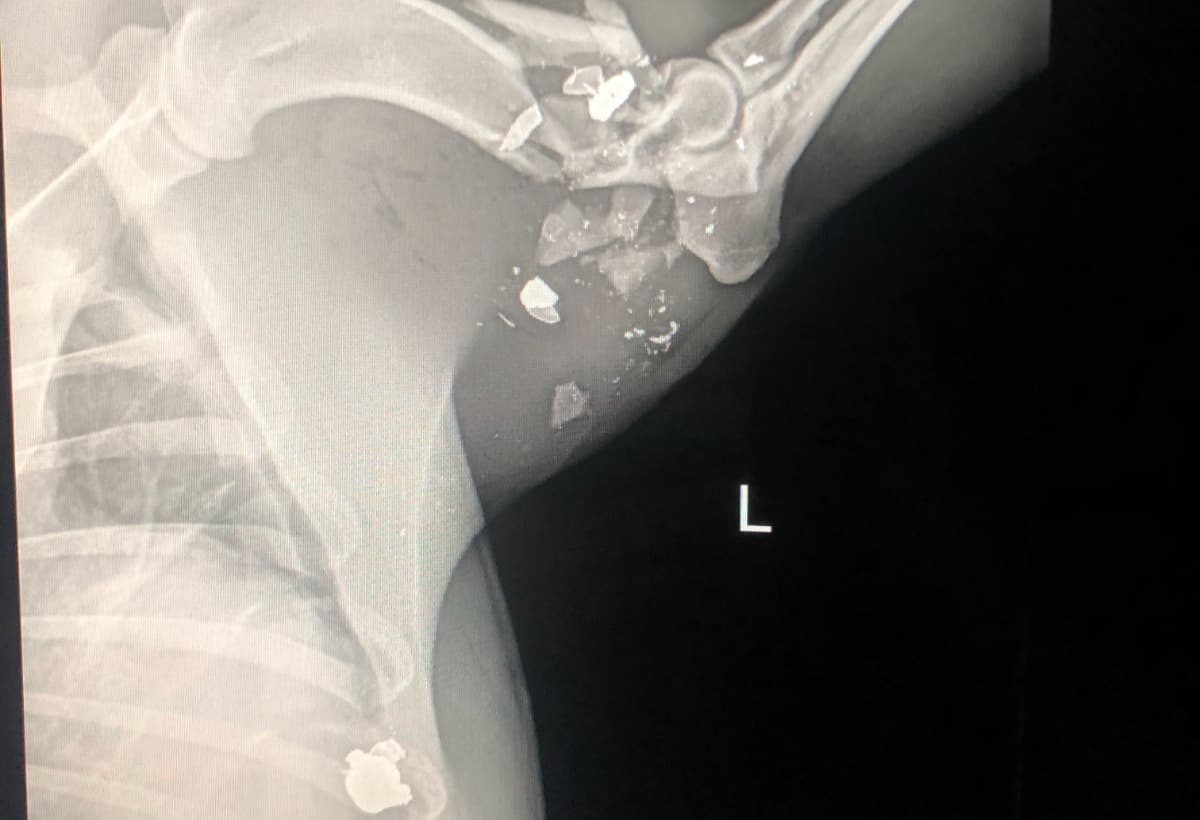

On August 13, 2021 at approxamitaley 10 a.m. I was woken up to all of my dogs going crazy which is something that is very unusual and out of the ordinary. I jumped up out of bed to see what all the commosion was and the first thing i see when i open my back door was my baby boy euro leaning against my patio door lifting his leg bleeding out . I was stunned with confusion as to how this happened and what was going on! i looked to my left and seen my neighbors heading back in their home, after i paid my attenton to my poor euro who was badley wounded I immediately picked him up to get him cleaned up and it looked like he had took a blood bath. i went back in my home partially ripped my curtains off my window and placed them on the floor along with him on top. With me panicking cleaning him up trying to figure out how this happened i went outside to look for answers. i calmly walked over to my next door neighbors house knocked on their door only for them to be hiding behind there front door. As i walking over back to my house upset , i was stopped by my front neighbors roofer worker, my front neighbor was getting his roof worked on By a roofing company when all of this happened. keep in mind i was asleep when all this happened as well. I had a group of 10+ workers come to me saying they witnessed my neighbor calmly walk to the sideline of the fence that seperates mine and his yard and fired his weapon at my poor dog who was under the tree minding his buisness. When i heard that i was raging with anger and walked back over and said some foul language i mean who wouldnt right? I started thinking about my reaction and behavior and stopped ran back home to get my boy some help. Me and my brother then loaded him up onto the truck and immediatley rushed to the closest Aniaml ER. Only then to hear the news that his bones were in pieces and our only options was to umputate it or put him down. not only that we were handed a enourmes Vet bill for the procedure and for the time and labor it was like a hammer hitting you back to back. As we waited outside the Animal ER trying to figure out what to do A Kind Police officer passed us and Seen the sorrow in our faces and may have seen all the blood we were covered in as well and asked about our situation. He wanted to take matter in his hands as fast as he could, so we rushed together back to the scene and got all the information he needed. We are in a desperate time of need and i hate to do stuff like this but anything at this moment helps . as of august 14 at approximietly 8:19 a.m. we were notifed By Dr.Marcus that our boy euro made it through surgery and has a long road to recovery ahead of him. This is just the beginning of his new life. He now has alot to adjust to because of the descision's and foul action my neighbor decided to do. thank you for the time you guys took to hear my story i wouldnt wish this upon anyone else. Again thank you for you time and concerns.